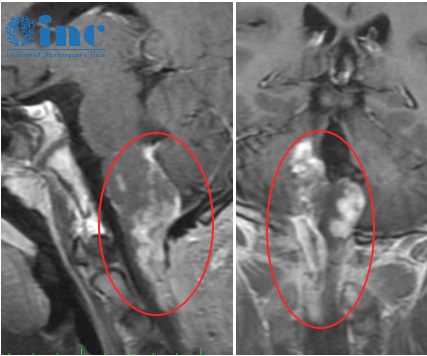

核磁結(jié)果令一家人陷入絕望,檢查結(jié)果顯示頸髓、延髓、右側(cè)小腦腳占位。醫(yī)生建議手術(shù)切除,在國內(nèi)醫(yī)院進(jìn)行了開顱手術(shù),然而情況并不樂觀,由于腫瘤位置處于延髓,較其困難,術(shù)后亮亮的情況并沒有得到好轉(zhuǎn)。

國內(nèi)行一開始開顱術(shù)后影像

由于亮亮的腫瘤復(fù)雜呈現(xiàn)彌漫生長,侵犯范圍廣泛,在保神經(jīng)下大部分的腫瘤得到了切除,壓迫延髓的腫瘤得到全部切除、解除了腫瘤進(jìn)一步壓迫腦干導(dǎo)致癱瘓、昏迷等風(fēng)險。巴教授手術(shù)中順利切除了壓迫腦干的腫瘤組織,對椎管和顱頸交界區(qū)進(jìn)行了很好的解壓,使得腦干-延髓和頸髓得以恢復(fù),解除了腦干受壓導(dǎo)致的致命危險,為亮亮后續(xù)進(jìn)一步治療爭取到了更多的時間和機(jī)會。